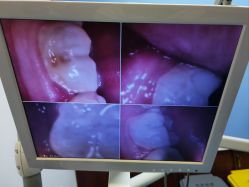

• 南京医科大学友谊整形外科医院

• -南京医科大学友谊整形外科医院

桂皮炝葡萄籽 上传于 23-01-12 | 报错

匿名用户 上传于 23-01-12 | 报错

• 体验后-南京医科大学友谊整形外科医院

体验后

*团团*_8033 上传于 23-01-02 | 报错